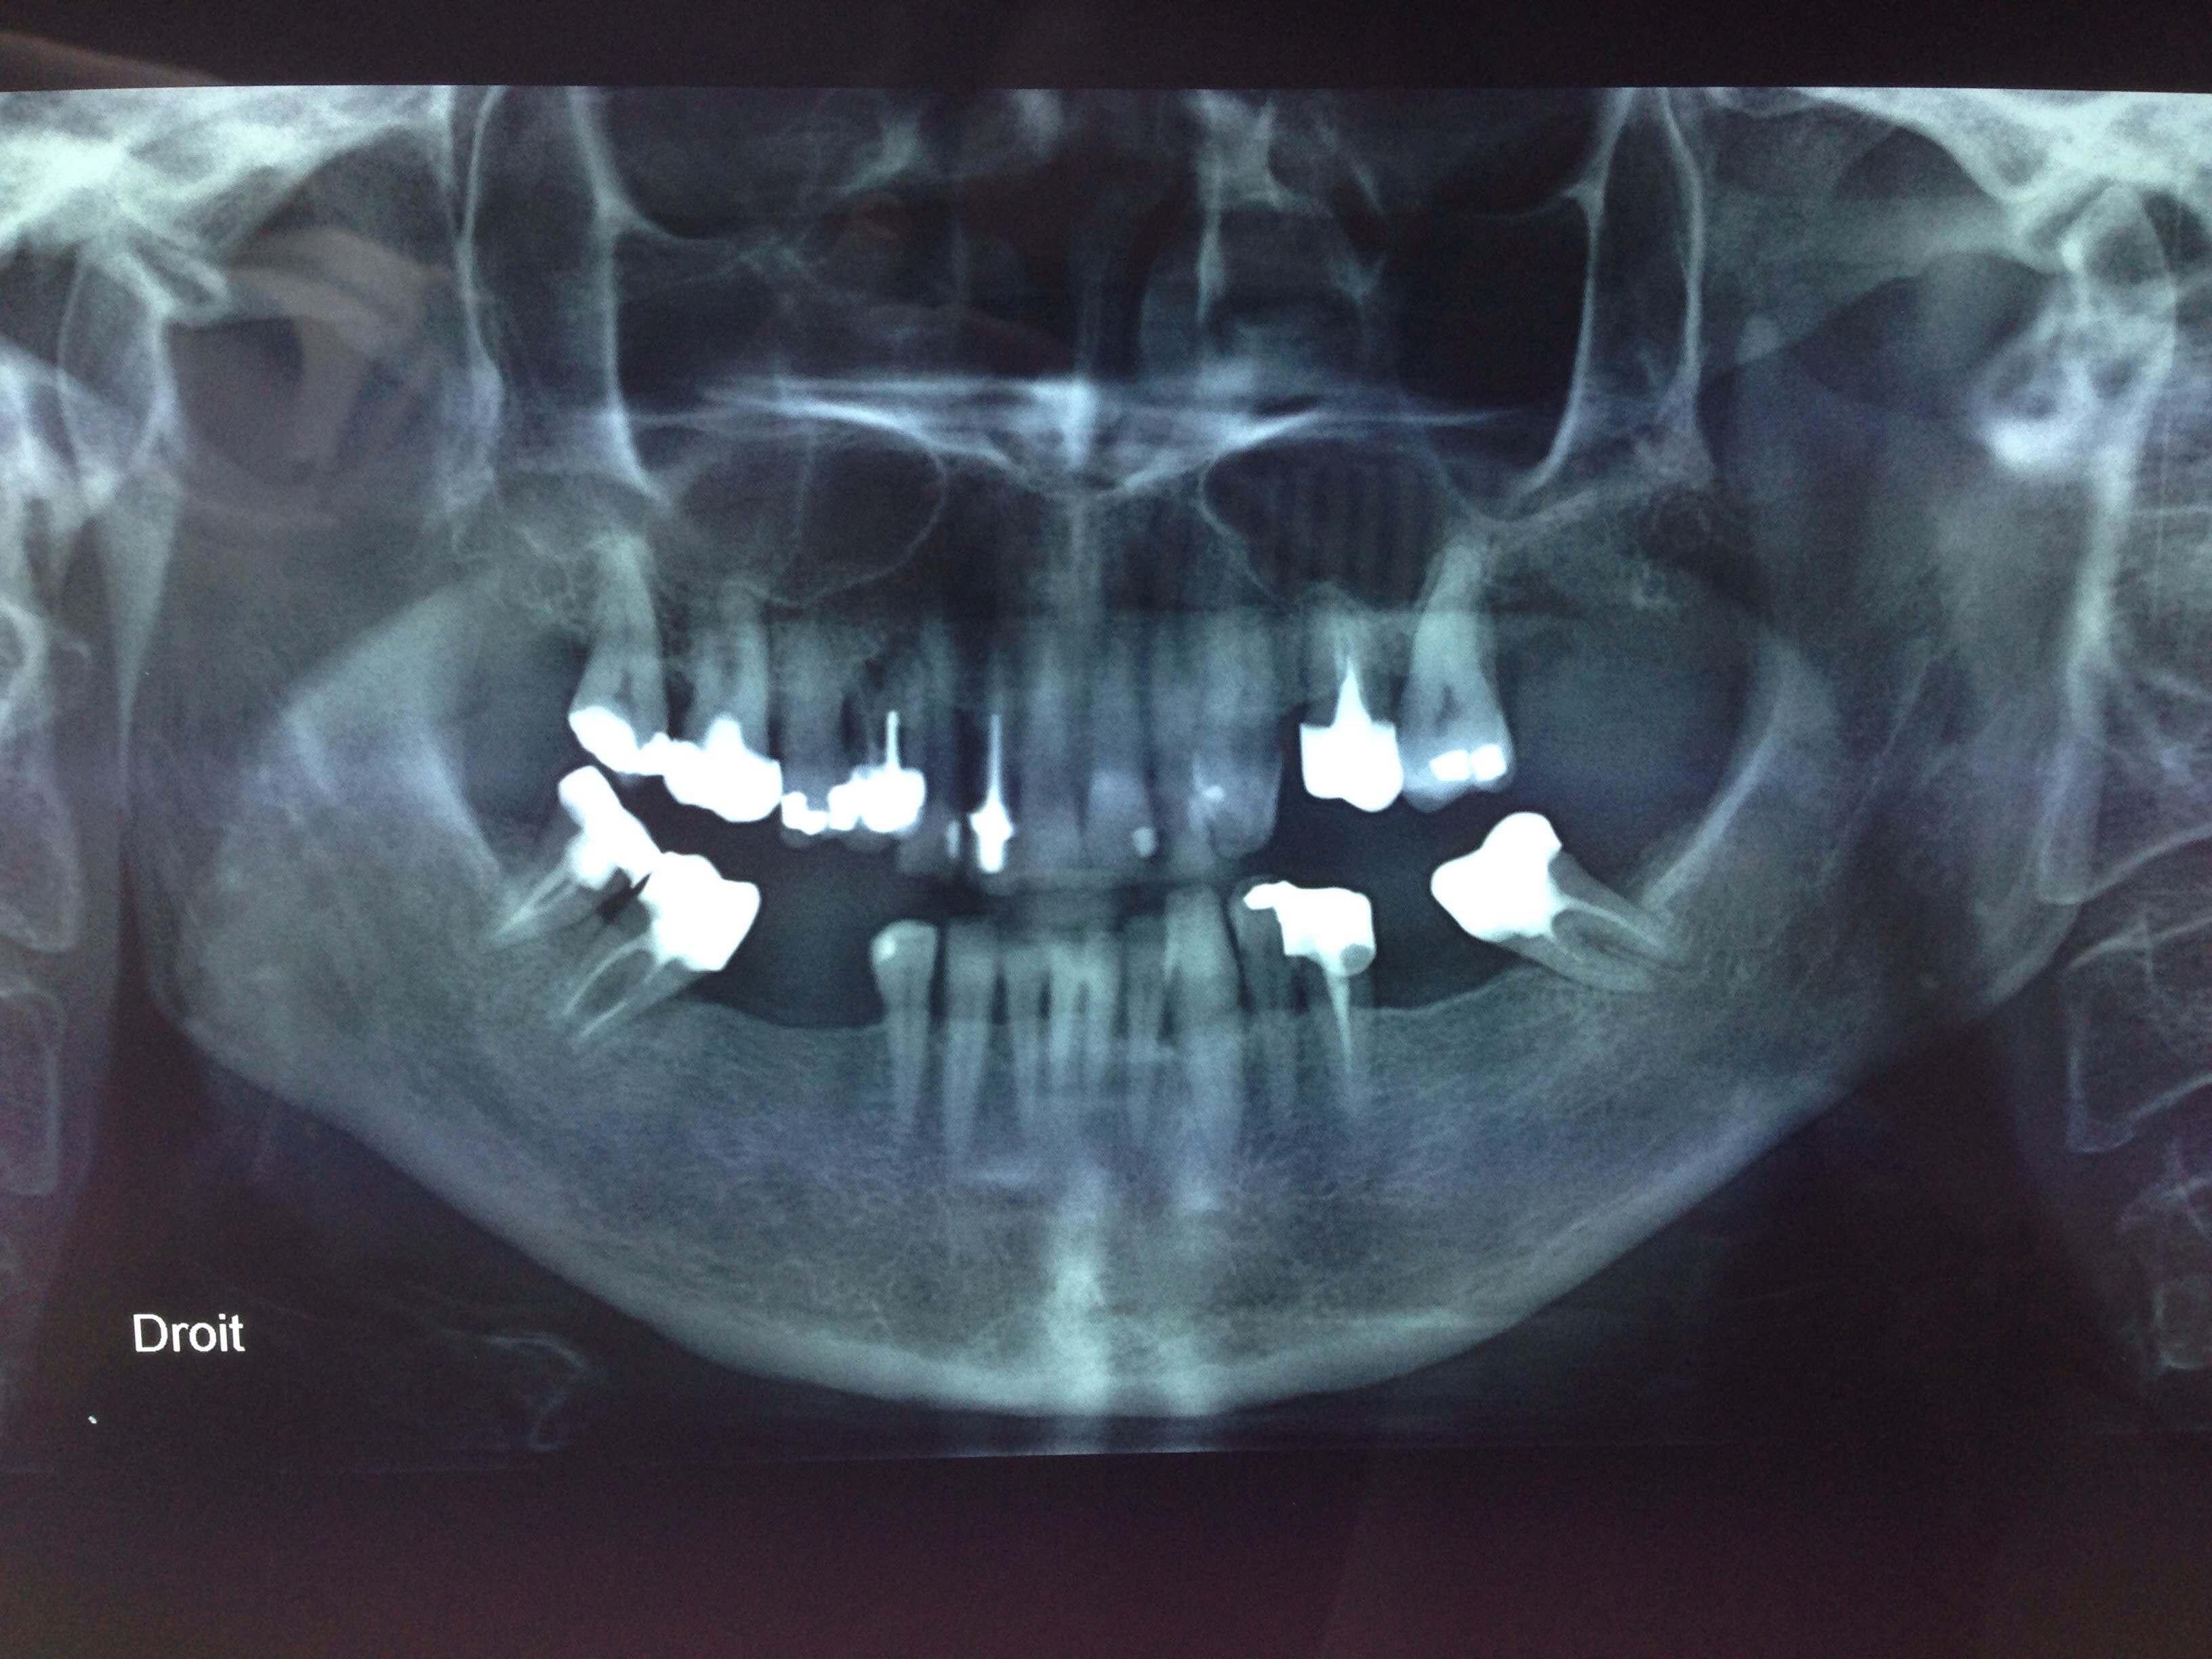

Voilà la pano :

Image xtpebm - Eugenol

ca parle pas trop

pas d'anomalies majeure a part la grosse patate sur 14

et contrôle de 23 (resorpt ou artefact)

oriente vers une centre anti douleur à mon avis : neuropathie probable

14 pas nette, à vérifier avec une rétro. Si vraiment il n'y a rien à ce niveau faire un questionnaire DN4.

47 meriterait quand meme qu'on s'attarde un peu plus sur elle.

Je te parle pas de 16 qui a une magnifique pulpotomie depuis Pompidou, 48 endo-CC (comme si ca servait a quelque chose) et 14 qui partira avec le prochain nougat, mais ca c'est que a droite et infectieux apres tu as tout le reste....